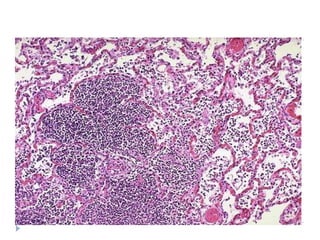

   Bronkopnömoni: yama tarzında konsolidasyon

LOBER PNÖMONĠ

BRONKO

PNÖMONĠ

Toplum içinde edinilenakut pnömoni morfoloji  Bronkopnömoni: yama tarzında konsolidasyon  Lober pnömoni: bir lobun tamamının tutulumu  Konjesyon  Kırmızı hepatizasyon  Gri hepatizasyon  Rezolüsyon  *Klinik açıdan önemli olan etkenin belirlenmesi ve hastalığın yayılımının belirlenmesidir